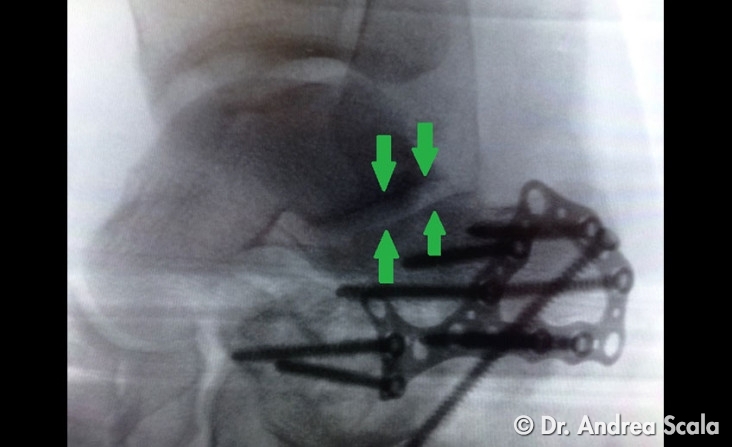

Alla fine dell’intervento il risultato della ricostruzione dell’articolazione del calcagno è stata soddisfacente. Le frecce verdi sulla radiografia post-operatoria fanno capire come è stata ricostruita l’articolazione, che era crollata al momento della frattura. La placca e le viti assicurano la stabilità della ricostruzione.